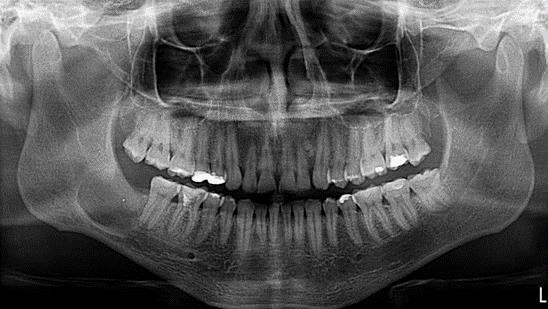

-          Enfermedad actual: hallazgo radiográfico ocasional , desde febrero (2014) en zona retromolar, mandibular derecha, al  examen físico se evidencia desgastes de los bordes incisales tanto superiores como inferiores, halitosis, caries y restauraciones defectuosas, refiere mal sabor que aparece y desaparece, sin dolor, a la tactación se evidencia expansión de la tabla lingual de la zona del 48, al examen radiográfico de tipo panorámica normal,  se evidencia imagen radiolúcida de bordes definidos que compromete el canal mandibular, de progresión lenta, se indica TAC, y exámenes de laboratorio.

Figura. 1. Ortopantomografía inicial, hallazgo ocasional. Fuente Palima (2016).

Se procede al llenado de historia clínica, revisión        clínica,           valoración     de ortopantomografia, dado el hallazgo, los signos y síntomas clínicos presentes se indica TAC, exámenes de laboratorio, toma de fotografías extra e intraorales, para el análisis y presentación del caso clínico.